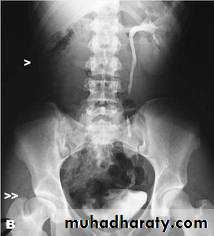

( PUJ OBSTRUCTION ):IVU shows :

Marked dilatation of pelvis and may be extra-renal.

Calyceal dilatation is late and in advanced cases form foot shape PCS

The ureter is not seen and when it is seen looksnormal .

Delayed film with I.V. diuretic produce gross dilatation .